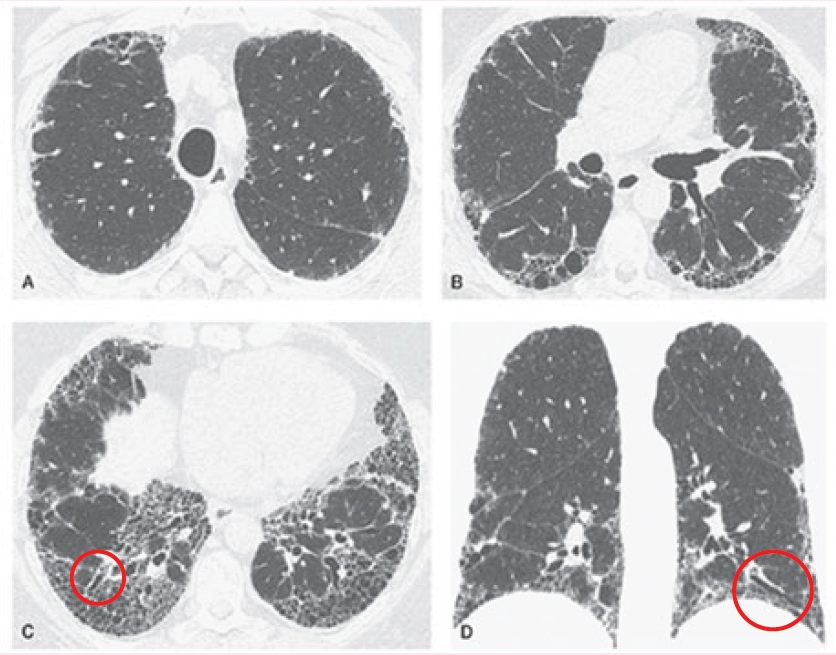

尋常性間質性肺炎(UIP),經高解析度電腦斷層(HRCT)檢查,纖維化的影像可分成以下四類型:

典型的UIP之HRCT影像(A-C為橫切面,D為重組冠狀面),顯示雙側肺部出現網狀結構和肋膜下蜂窩狀變化(肺纖維化的表現),且呈現顱尾分布,主要分布於外圍及基底部。雙下肺葉可見牽引性支氣管擴張(紅圈處)。High-Resolution CT of the Lung (2021)